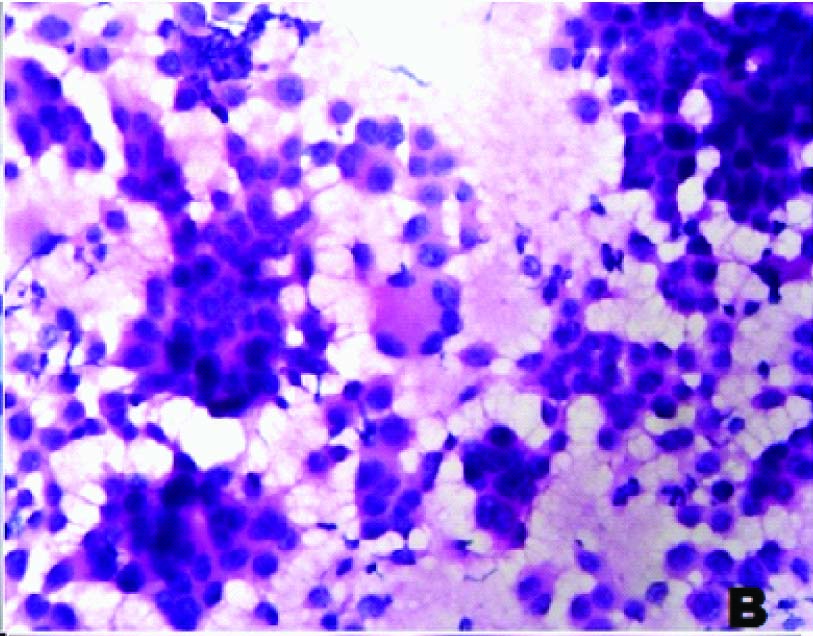

A 55-year-old male patient presented with pain abdomen and multiple skin nodules over the anterior abdominal wall and left cervical lymphadenopathy. On local examination, the abdominal skin nodules were firm to hard in consistency and the largest measured 3 x 2 cms. The left cervical lymph node was single, discrete and firm to hard in consistency. FNAC was performed on the abdominal skin nodules and the left cervical lymph node. FNAC smears studied from both the left cervical lymph node and the abdominal skin nodules showed similar cytological features. The smears were highly cellular and showed predominantly dispersed cell population of uniform tumour cells [Table/Fig-1a] in sheets, clusters, rosettes and tumour balls [Table/Fig-1b]. The cytoplasm was moderate, eosinophilic and granular. The nuclei were round to oval, with stippled chromatin and inconspicuous single prominent nucleolus [Table/Fig-1c]. Plenty of atypical mitoses were present [Table/Fig-1d]. In addition, many multinucleated giant cells and bizarre tumour cells were seen. Extracellular eosinophilic basement membrane- like material was also seen [Table/Fig-2a].

FNAC of cervical lymph node showing monomorphic tumour cells (MGG, ×1000)

FNAC of skin nodule with tumour cells in rosettes (H&E, ×400)

FNAC showing tumour cells with eosinophilic cytoplasm and fine nuclear chromatin (H&E,×1000)

FNAC showing atypical mitotic figures (H&E,×1000)